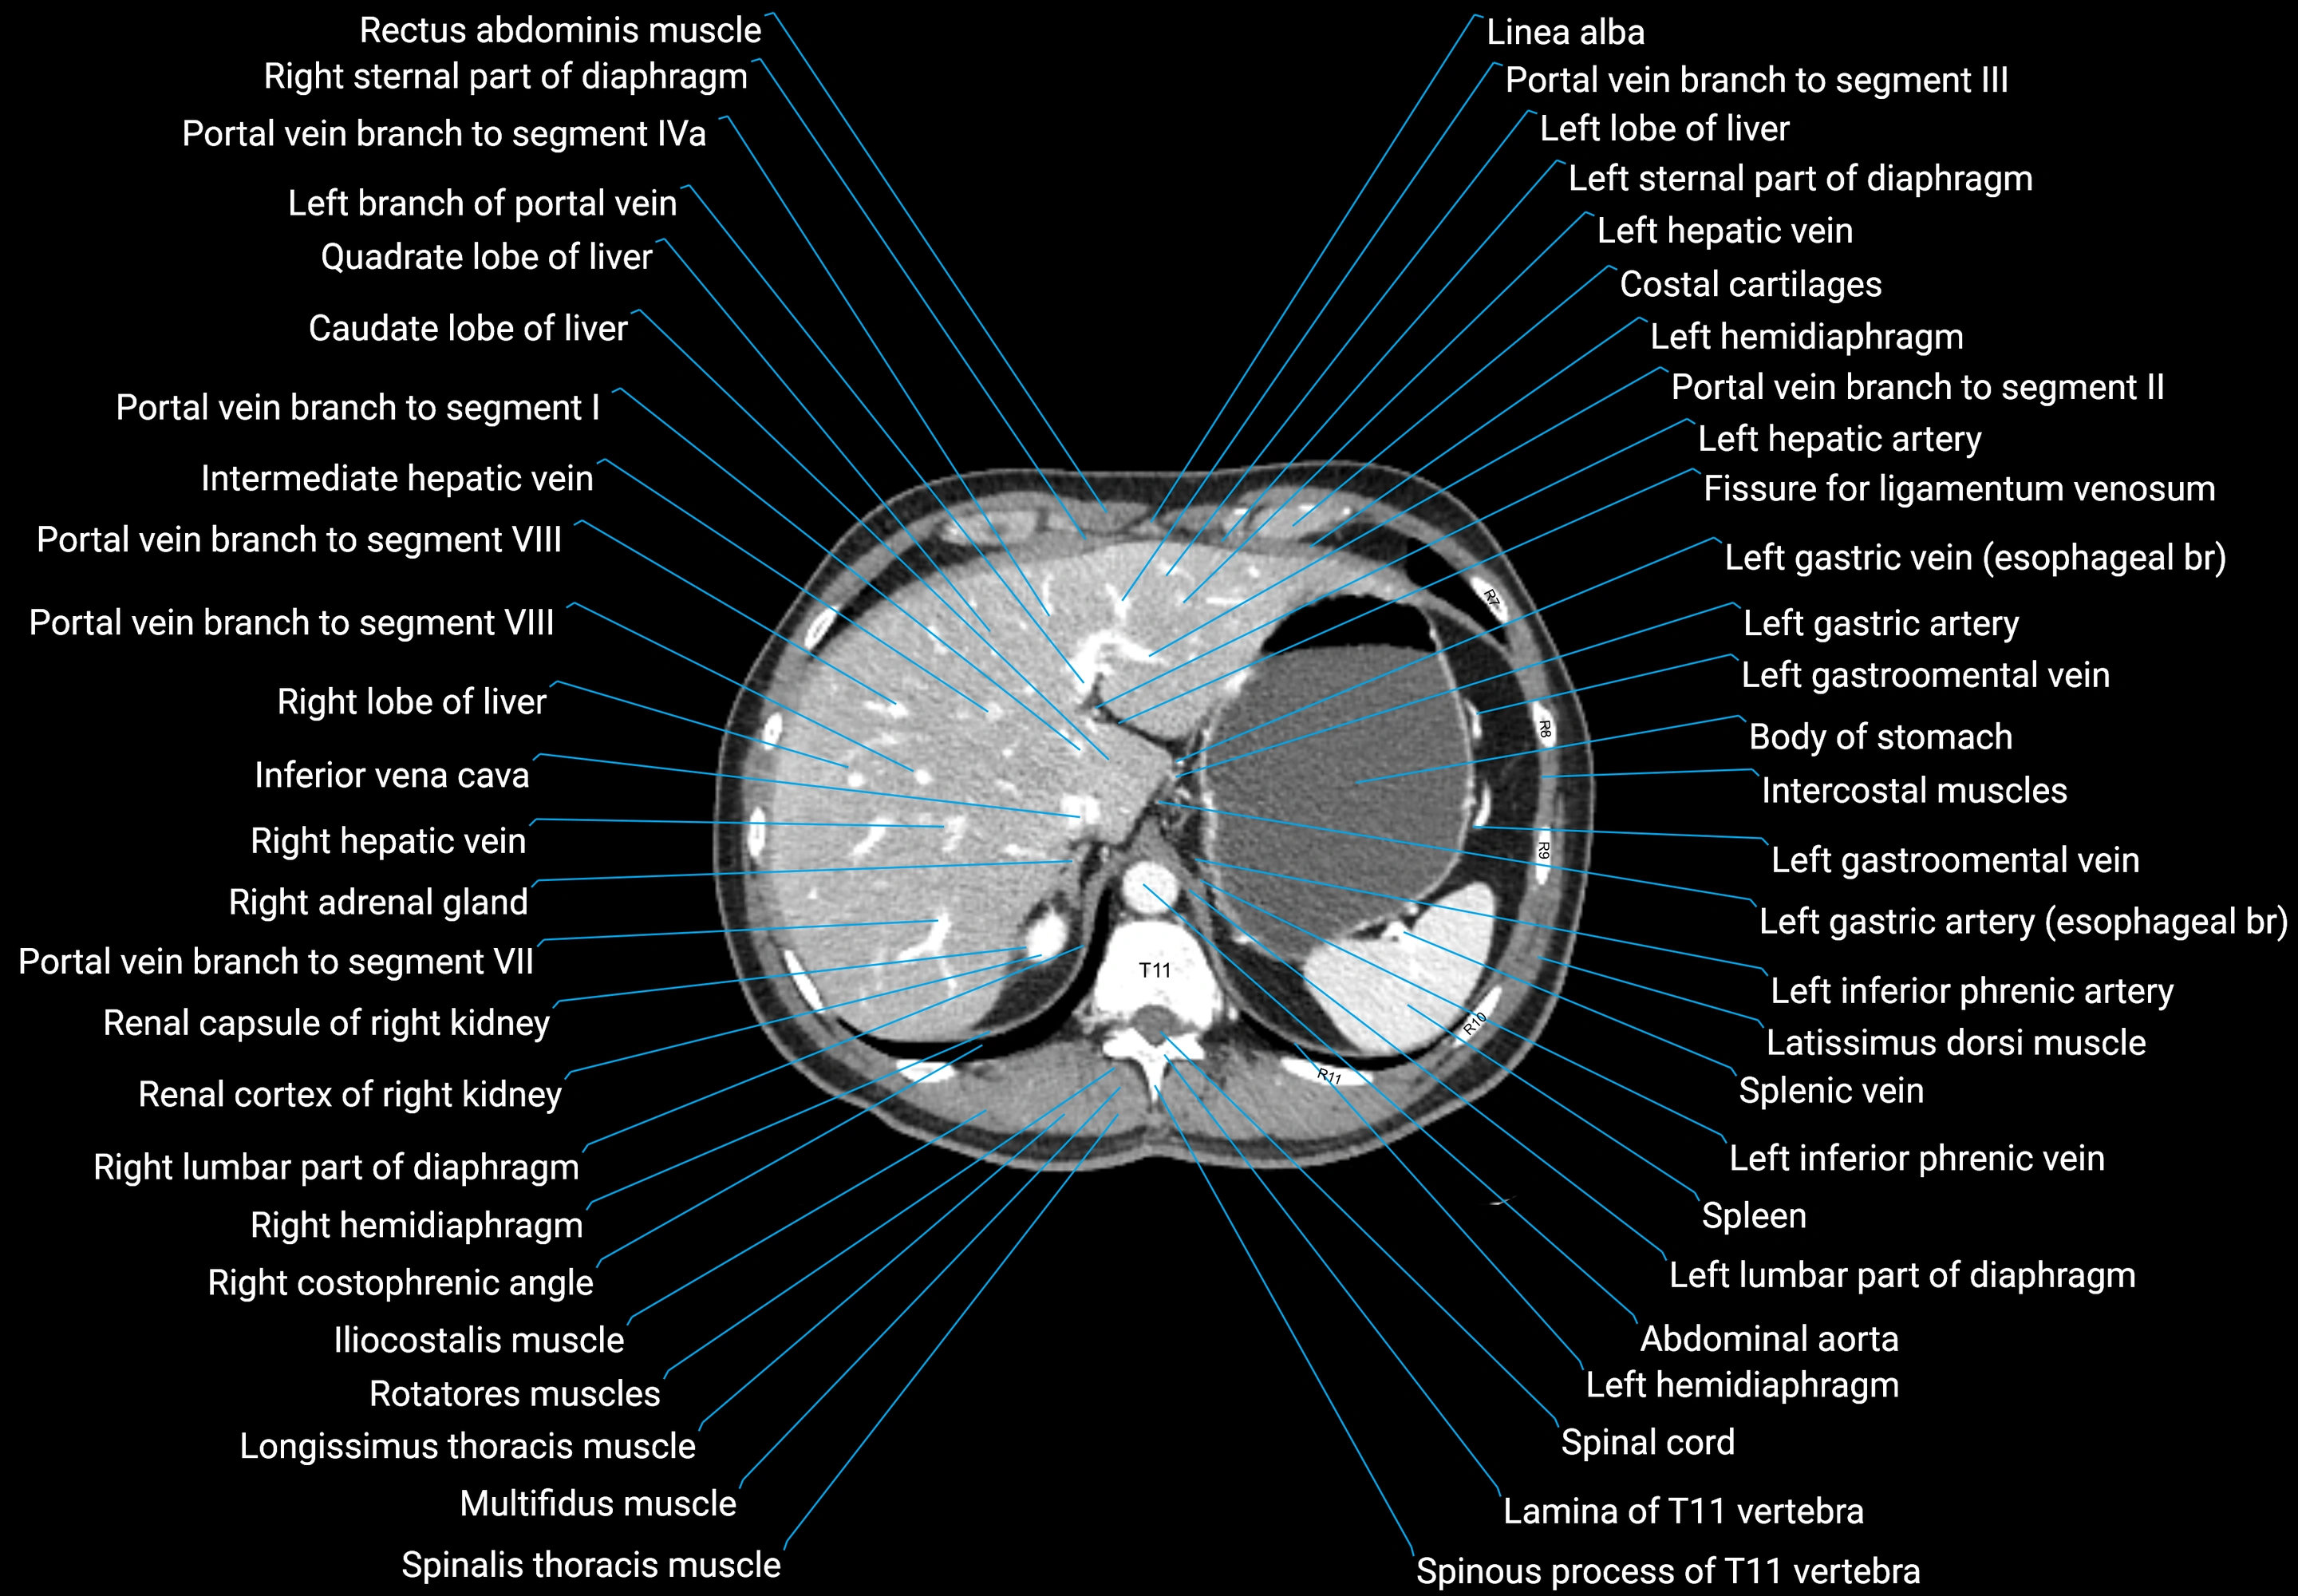

CT images